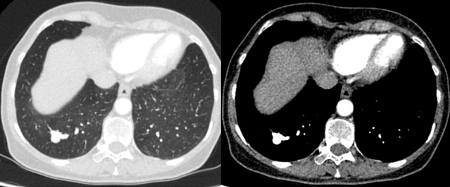

PET CT scan with 18-fluorodeoxyglucose (18-FDG) showing a high uptake peripheral left lung lesion. Surgical resection confirmed a moderately differentiated squamous cell lung cancer

From the collection of Dr George Tsaknis, MD, PhD, FRCP(London), MRQA, MAcadMEd, PGCert; used with permission